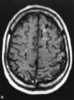

Juxtacortical chondroma